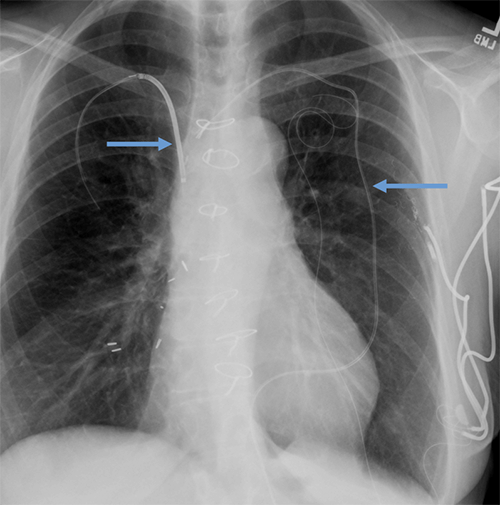

- CEID images with lead types:

Pacemaker with transvenous leads